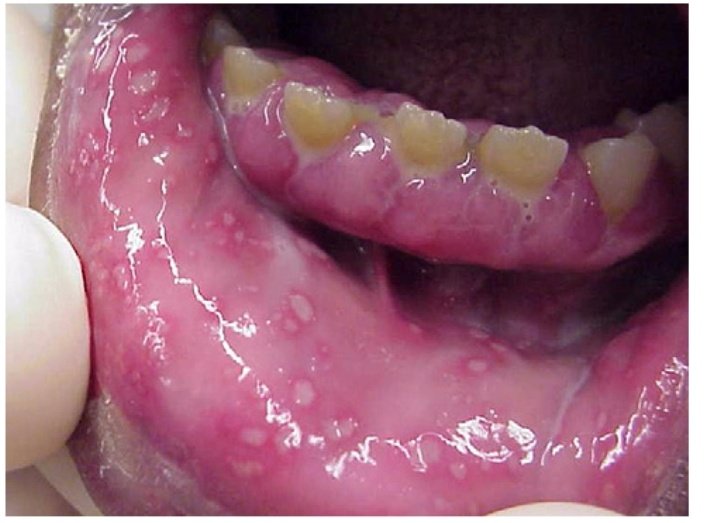

القرح القلاعية (Oral aphthous)

هي تقرحات مؤلمة متكررة، تكون منفردة او متعددة من ناحية الكم. هناك نوعان من القرح النوع الصغير (عدة مليمترات) الأكثر شيوعاً

والنوع الكبير (اكبر من نصف سنتيمتر) #مع_دكتور_عصام

تظهر القرحة في حوالي 20 ٪ من السكان. سبب القرحة غير معروف. يمكن أن تظهر القرح في أي مكان في الفم باستثناء الحنك واللثة.